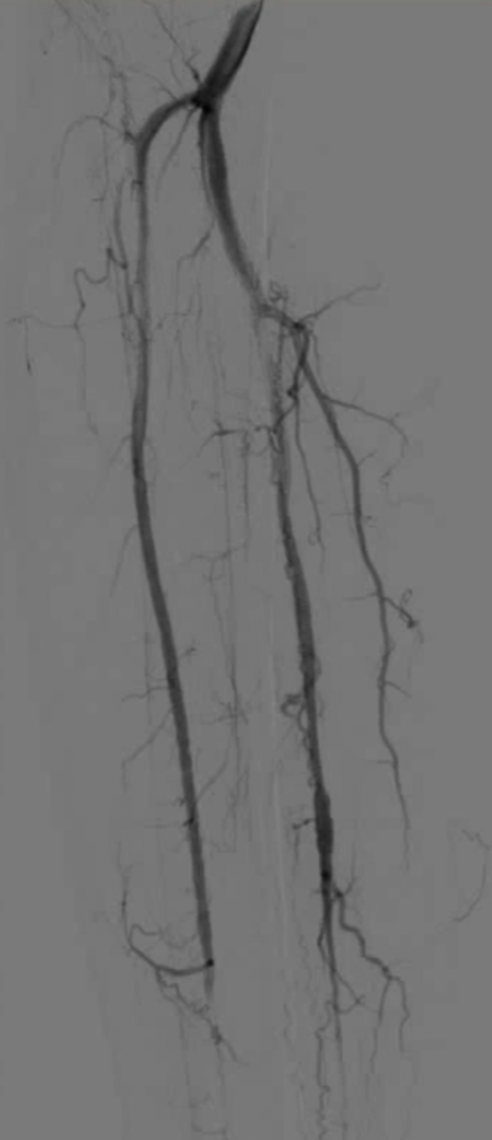

48岁男性,右足溃疡反复发作,多次PTA+DCB治疗

2023.3 右足部溃疡2个月,行PTA

2024.5,再发溃疡4个月,先后两次PTA

2024.9,溃疡未愈合,胫前动脉、胫后动脉PTA+DCB